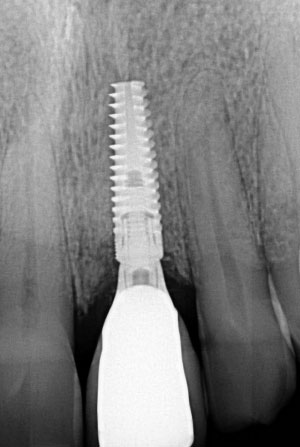

Immediate Implant UL1

After

All stages of surgical and restorative work by Mr RS Khurana